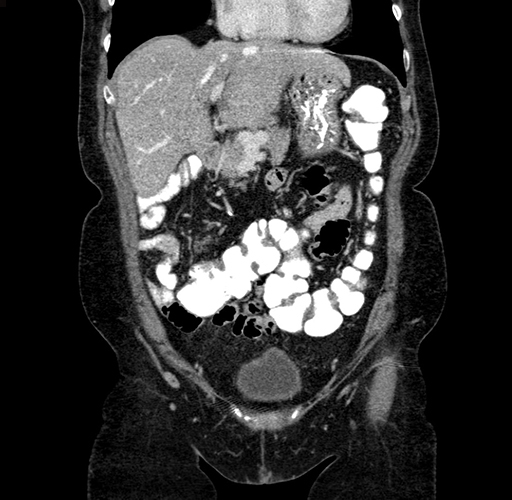

Pre-Chemo: Coronal Venous